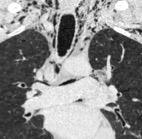

Raro. (2-9% de los T. tímicos). Asintomático. Contiene grasa (hasta 90%) y tejido timico (10-33%). Pueden ser muy grandes y confundirse con cardiomegalia. La tomografía “clásica” muestra los límites de la silueta cardiaca. (flechas)